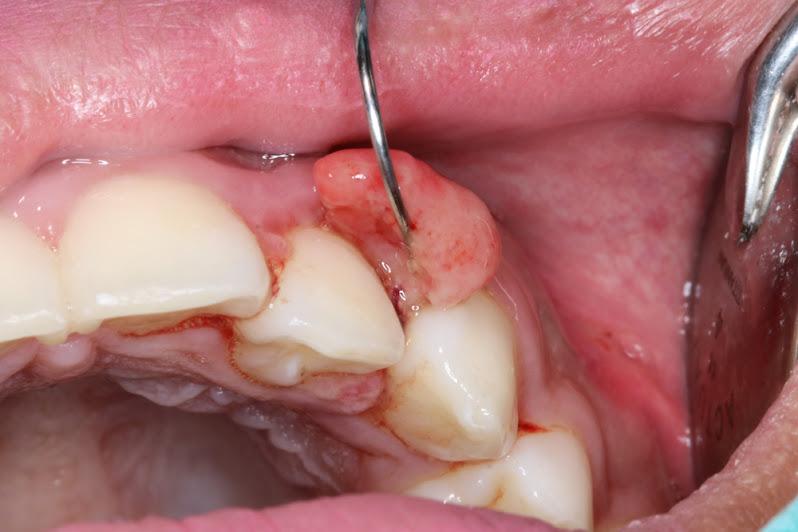

Fibroma oral adalah benjolan kecil yang merupakan tumor jinak non-kanker pada jaringan fibrosa di dalam mulut.

Jenis fibroma ini kerap disebut irritation atau traumatic fibromas karena biasanya disebabkan oleh iritasi atau trauma di area tersebut.

Meski bisa tumbuh di semua bagian mulut yang memiliki jaringan fibrosa, traumatic fibroma paling sering terbentuk di pipi bagian dalam, tepatnya area pertemuan gigi atas dan bawah.

Laman Cleveland Clinic menyebutkan bahwa benjolan fibroma oral memiliki tekstur halus dan berwarna sama dengan bagian mulut lainnya.

Meski begitu, tak jarang warnanya lebih pucat atau justru lebih merah karena berdarah ketika bergesekan dengan sesuatu yang masuk ke mulut.

Sebagian besar benjolan fibroma berbentuk bulat kecil seperti kacang polong dan hanya tumbuh sebagai lesi tunggal, tidak bergerombol. Namun, fibroma mungkin tumbuh di beberapa area sekaligus.

Meski ukurannya mungkin mencapai 1 cm, benjolan ini seharusnya tidak terasa sakit. Fibroma juga tidak akan berkembang menjadi tumor gusi atau kanker mulut.